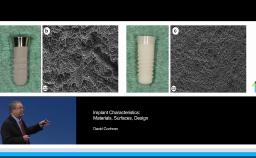

This presentation discusses the evolution of dental implant designs and the effects of various designs on peri-implant tissues. The biologic width around natural teeth is compared to the biologic width around implants. The main contemporary implant systems and types are discussed, and sound research is presented to explain the current understanding of dental implant components and macro designs. Butt joint, tissue level, and platform switching designs are compared, as well as external hex and internal conical implant-abutment connections. Biologic effects of different designs are presented, and clinical advice based on basic research is given at the conclusion.

- describe different types of dental implant designs

- recognize the effect of dental implant designs and components on the surrounding tissues